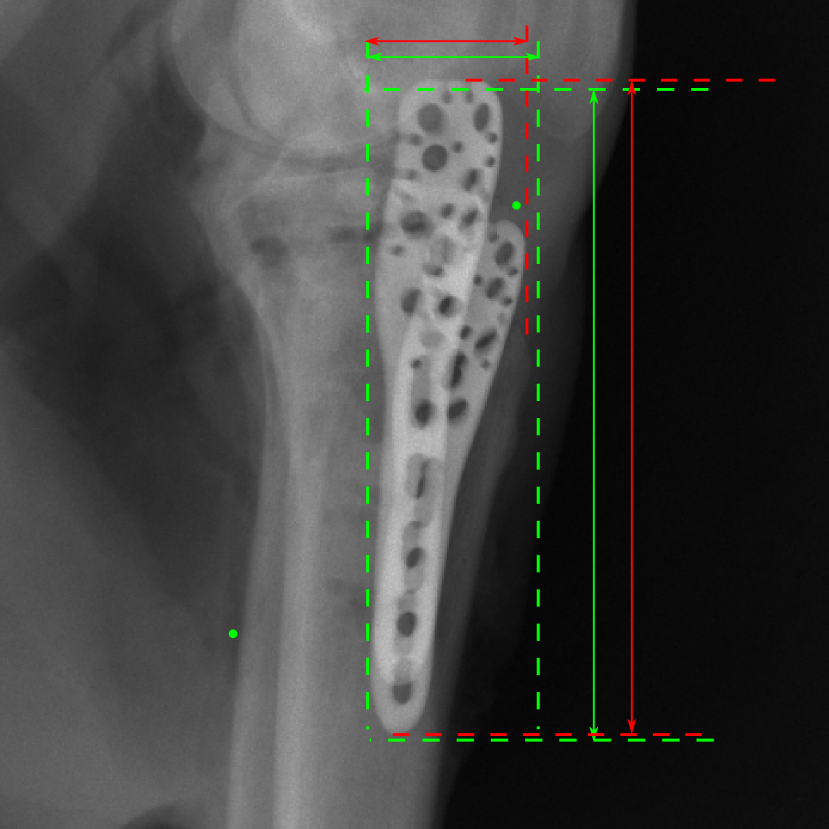

5.4 Real Knee Data with Metal Implants

Refer to caption

Figure 13: Three examples of synthetic perspective projection images for training, intensity window: [0, 4]. The appearance (e.g., image contrast and metal image resolution) of such DRR training images is different from that of real projection images in Fig. 14.

0superscript00^{\circ} perspective

Figure 14: The results for the real cadaver leg data. The green dots mark the positions of landmarks in the corresponding reference images. In the first column, the arrows indicate the bone cavity/fracture structures. In the second column, the solid lines mark the widths and heights of the metals. The green ones are measured from the DRR reference, while the red ones are measured in the corresponding perspective projection image. In the last column, the lines mark the centerlines of the metal screws, where the green lines are those from the reference image. The lengths of the lines in mm are displayed in their corresponding subcaptions. Intensity window: [0, 4]. Please zoom in for better visualization.

The complementary view setting for learning perspective deformation is also evaluated on real CBCT projection data. In this evaluation, real CBCT projection data from a dataset of knees with metal implants is used for testing, while DRRs created from volumetric CT datasets with inserted metals is used for training. Three exemplary DRR perspective projection images for training are displayed in Fig. 13, in which synthetic metal implants are inserted [34]. The appearance, e.g., image contrast and metal image resolution, of such DRR training images is different from that of real projection images in Fig. 14. In Fig. 14, the results for three knees, with and without metal implants, are displayed. The first and second rows are the 0superscript00^{\circ} and 180superscript180180^{\circ} perspective projections, respectively, rebinned to the virtual detector with geometric calibration based on their respective principal points and projections of the world origin. The third row displays their difference images, where the magnitude of deviation increases from the center towards the outside like it does in DRRs with an ideal scan trajectory (e.g., Fig. 6(e)), although real projection data suffer from various physical effects like beam hardening and Poisson noise. The fourth row displays the RGB stacks of 0superscript00^{\circ} and 180superscript180180^{\circ} perspective projection images. The magenta and green regions indicate structures with considerable perspective deformation, for example, the knee patella in Fig. 5.4, the top parts of the two metals in Fig. 5.4, and the bottom two screws in Fig. 5.4. The fifth row displays reference images, which are orthogonal projections of iterative reconstruction volumes from measured CBCT projection data. In the reference images, a total of five landmarks are selected, with the positions being marked by the green dots: In Fig. 5.4, two positions at the edges of the knee patella are marked; In Fig. 14(e) and Fig. 14(f), one position at the left edge of the fibula is marked for each image. In addition, a rectangular frame for the two metals is marked by the green dashed lines, while its width and height are indicated by the green solid lines, which are 29.71 mm and 111.99 mm, respectively. In Fig. 14(f), the centerlines of the bottom two screws are sketched by the green lines, which have the lengths of 17.14 mm (middle screw) and 19.38 mm (bottom screw). The corresponding rectangular frame for the two metals and the screw centerlines in the perspective projection images are marked as well, but in red color. In Fig. 14(a), the width and height of the metals are 32.56 mm and 109.85 mm, which have deviations of 2.84 mm and -1.95 mm to the reference ones, respectively. In Fig. 14(b), the centerline lengths are 18.91 mm and 19.54 mm, which have deviations of 1.77 mm and 0.16 mm, respectively. Although the bottom screw has little length deviation to the reference, the orientations of both screws are obviously deviated. The sixth row shows the results of Pix2pixGAN using 0superscript00^{\circ} and 180superscript180180^{\circ} polar inputs. For all of the landmarks, the green reference dots are all located accurately in the Pix2pixGAN images. The rectangular reference frame also accurately covers the metals in Fig. 14(g). In Fig. 14(h), although the two red centerlines do not exactly overlap with the green one, they are very close in lengths and orientations. Please zoom in for better visualization.